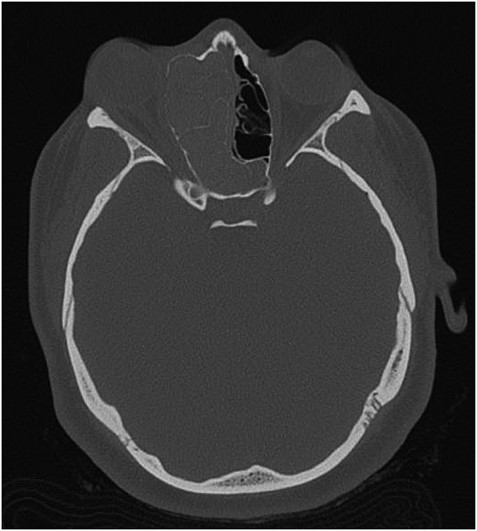

The results of the CT indicated complete opacification of the frontal, ethmoidal, sphenoidal and maxillary sinus on the right side with hyper-dense intraluminal soft tissue filling the sinus cavities. Significant widening of the ostiomeatal complex was observed (Fig. 1). Soft tissue from the right maxillary sinus extended into the right side of the nasal cavity. Extensive changes in the right ethmoidal labyrinth were also discovered. The intact lamella of the middle turbinate and lamella of the bulla ethmoidalis extended further laterally when compared to the left side, and lamina papyracea was protruding into the orbit (Figs 1 and 2). Options were discussed and endoscopic CT guided surgery was recommended.

Axial CT image indicating widening of the ostiomeatal complex with malformation of the right ethmoid.